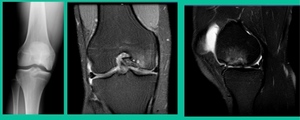

Now a couple of quick cases. This is juvenile OCD. This is the first series of three or four, just juveniles. 14-year-old, intermittent knee pain, lateral femoral condyle OCD (Figure 1).

This is an 11-year-old. Left knee lateral knee pain. Effusions, the same type of classic findings (Figure 3)

Another case example. 14-year-old male tennis player, 10 months of knee pain (Figure 7A).

This is a Trochlear defect (Figure 7B).